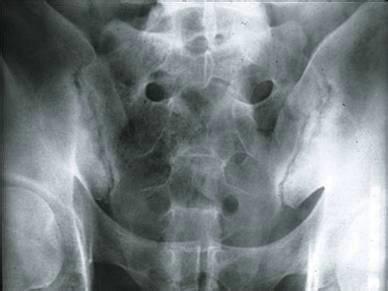

(图:X线片显示其双侧骶髂关节不规则变窄)

检查结果:白细胞偏多,血沉及C反应蛋白显著偏高,HLA—B27检查呈阳性,免疫球蛋白升高,类风湿因子阴性。骶髂关节X线片显示其双侧骶髂关节软骨下骨出现骨硬化、骨质增生、关节间隙变窄症状,脊柱X线片显示异常。